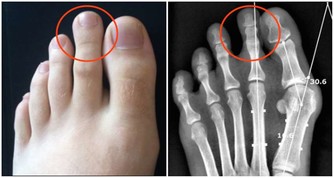

需要修趾甲的糖友,也必須在泡腳後趾甲較軟時再修剪,趾甲要平剪,不能剪成圓形,以免傷及甲溝。